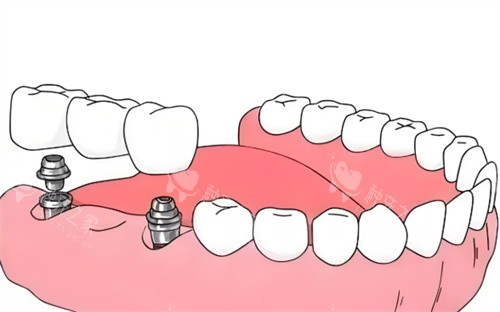

机构开展的VIIV穿颧种植技术,能够为重度骨吸收患者提供无需植骨的种植方案,有效解决牙槽骨量不足的种植难题。

他们在单颗种植、半口/全口种植、即刻种植、骨增量种植以及穿颧穿翼等高难度种植技术方面积累了良好的口碑。

对于半口牙齿缺失的情况,机构提供了更具性价比的选择:半口4颗种植低至需要15800元起,半口6颗种植价格也从20000元起。